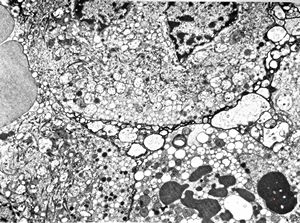

unclassified pancreatic tumor